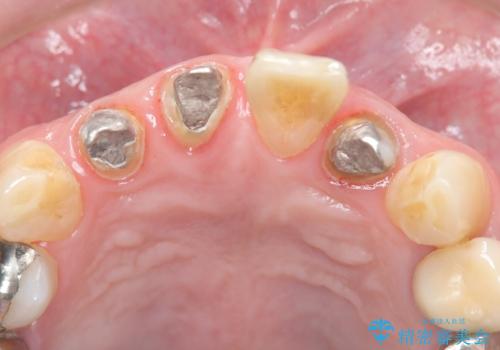

古い被せ物を除去しオールセラミッククラウンで治療を行いました。

被せ物の適合が悪く劣化もおこし色が変色している状態でした。そのため他の歯とも色が合っていませんでした。古い被せ物を除去し形を整えた後にオールセラミッククラウンで治療を行いました。

根っこの先端に病巣(根尖性歯周炎)があったため根管治療または抜歯してインプラントを提案しましたが、患者さんのご希望により被せ物の治療のみを行いました。